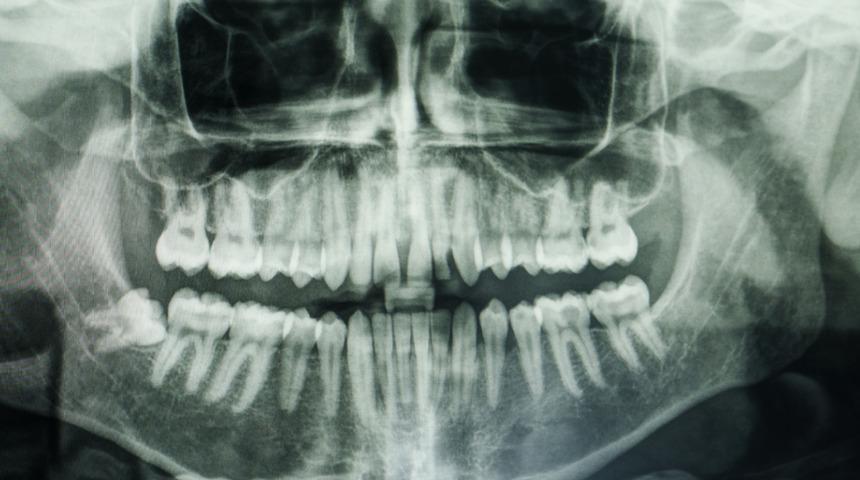

Bir kişinin ya da bir başkasının kemik dokusunun, hasar görmüş olan ya da kaybolan kemik bölgesine nakledilmesi işlemi kemik grefti olarak adlandırılır. Bu işlemin gerektiği çeşitli durumlar bulunur. Kemik grefti uygulaması genel olarak şu durumlarda yapılır:

• Diş implantları, kırıklar, kanser tedavileri nedeniyle oluşan kayıplarda,

• Çene kemiğinde eksik ya da deformasyon oluştuğu zaman,

• Diş kaybı olduktan sonra çene kemiğinin şekillendirilmesi için.